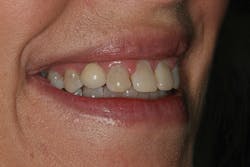

A comprehensive cosmetic, radiographic, and functional evaluation was performed.1 The patient was able to identify the major concerns leading to her dissatisfaction with her smile, including the presence of multiple diastemata, tooth proportion improprieties, unnatural emergence profile of her implant restorations, and her desire for a whiter smile (figure 3).2

Figure 3